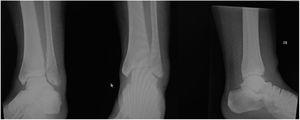

En el caso 2 se estableció como criterio quirúrgico el espacio claro medial aumentado de 5mm y la diferencia de 5 grados de el ángulo talocrural como se observo en las figuras 4 y 5,